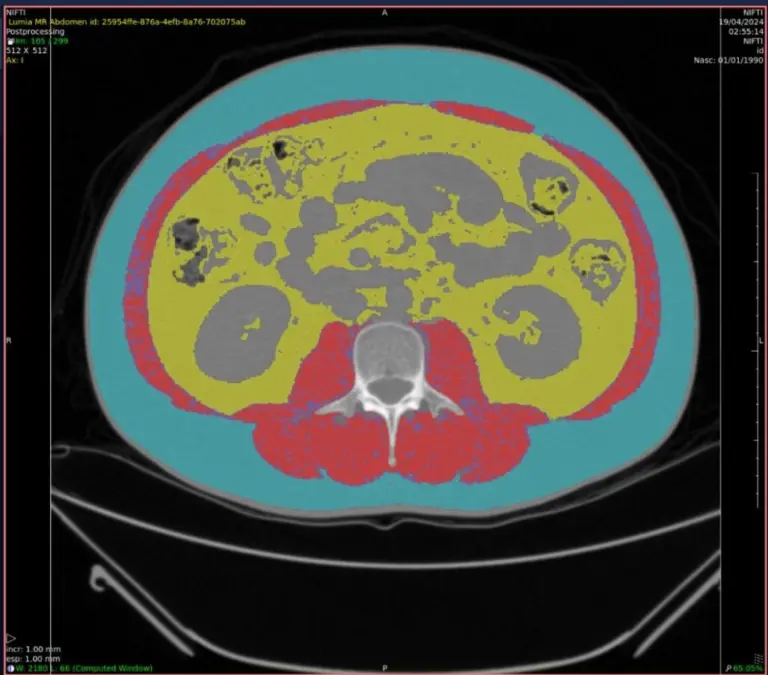

IA para cálculo de sarcopenia

Se clasifica como sarcopenia la alteración de la musculatura esquelética caracterizada por la reducción de la fuerza y de la masa muscular secundaria al envejecimiento, que compromete el desempeño físico del individuo.

Las herramientas de IA con esta especialidad pueden señalar hallazgos clínicos y realizar una medición automatizada de la distribución de grasa abdominal, acompañada de la evaluación de la masa muscular.